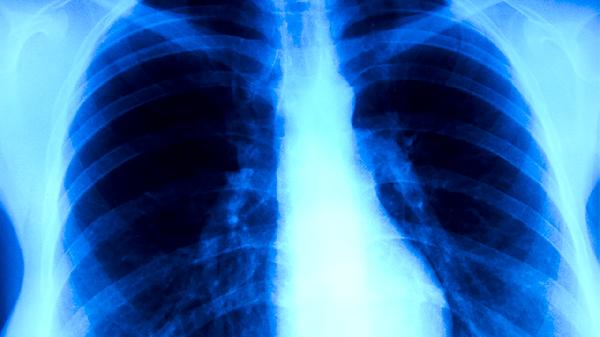

肺部肿瘤生长至一定体积时可能压迫迷走神经,该神经支配部分消化道功能。神经受压后可出现胃蠕动异常,表现为上腹饱胀、恶心等症状。临床需通过影像学检查确认肿瘤位置与神经关系,解除压迫是根本解决方式。